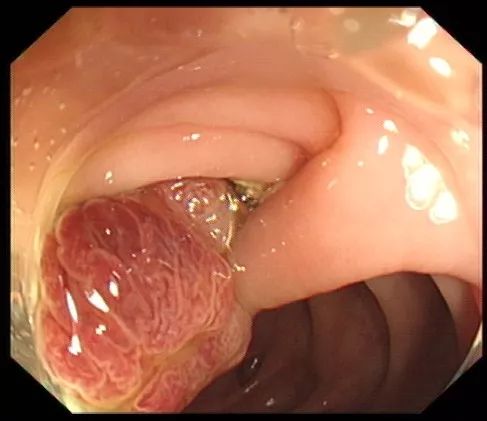

步骤二:通过肠镜上的孔道插入特殊器械(电圈套器),并在息肉旁伸出钢丝圈。

图片

步骤三:将钢丝圈套住息肉,并于息肉根部收紧钢丝圈。